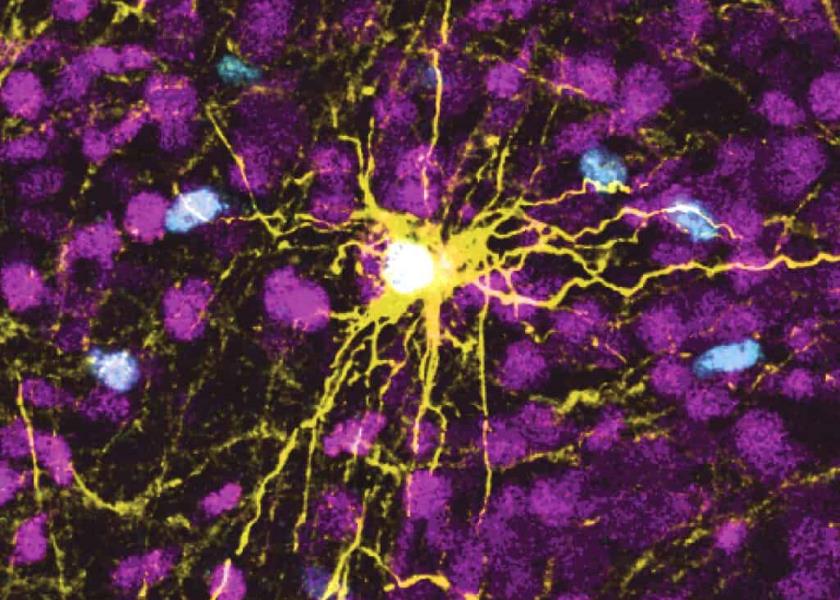

Para fabricar los organoides cerebrales, los científicos de la Universidad de Stanford trasformaron células de la piel humana en células madre y las manipularon para que se convirtieran en células cerebrales de diversos tipos. Estas células se multiplicaron para formar organoides similares a la corteza cerebral, la capa exterior del cerebro humano, asiento de funciones cruciales como la memoria, el pensamiento, el aprendizaje, el razonamiento y las emociones.

Los científicos trasplantaron esos organoides en ratas de dos a tres días de edad, una etapa en que las conexiones todavía están en proceso de formación. Estos organoides crecieron hasta ocupar un tercio del hemisferio del cerebro de la rata donde fueron implantados. Las neuronas de los organoides formaron conexiones funcionales con los circuitos en el cerebro.

No es la primera vez que se implantan células humanas en roedores, pero generalmente en ratones adultos. Pasca, profesor de psiquiatría en la Facultad de Medicina de Stanford, dijo que es la primera vez que se implantan estos organoides en cerebros de ratas jóvenes para crear "los circuitos cerebrales humanos más desarrollados que se hayan creado a partir de células de la piel humana y una demostración de que las neuronas humanas implantadas pueden modificar la conducta de un animal".